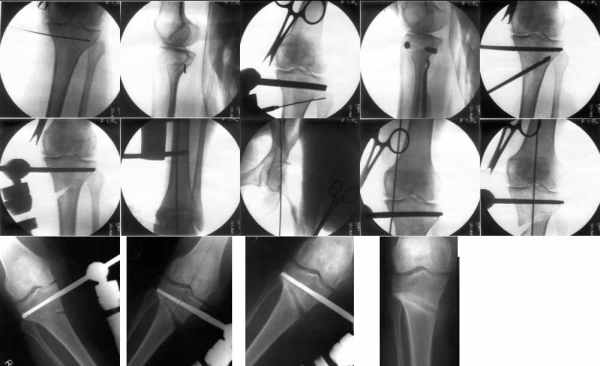

Картинки - в приложении.Будут вопросы - готов ответить.

Вот ещё картинки, которые отправлял в Ортопод. Коррекция кривизны и удлинение на 3 см.